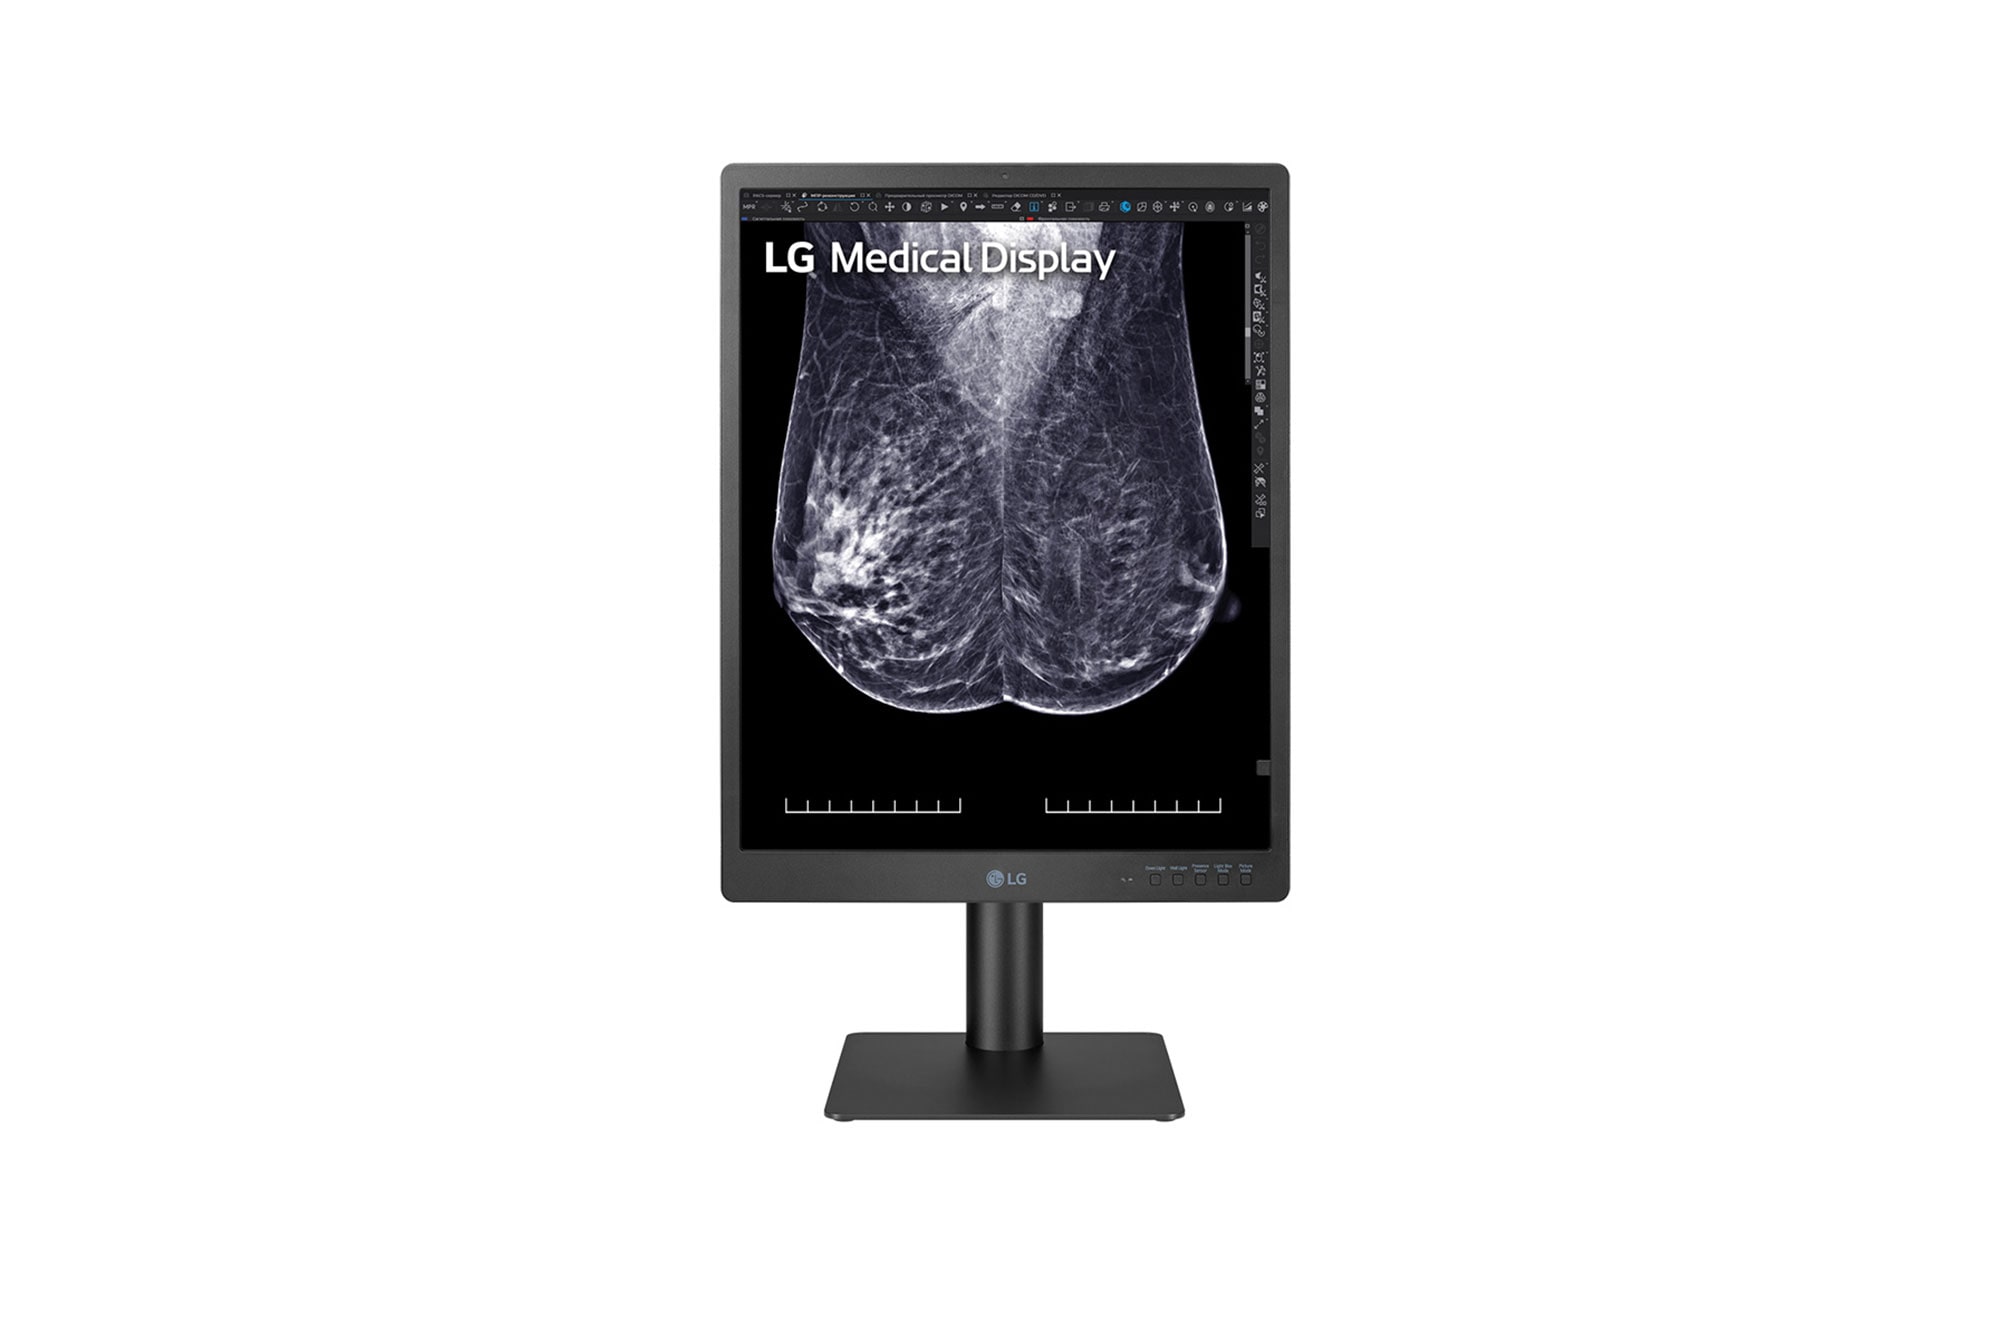

Display for breast imaging

21.3 (54.102 cm) 5MP (2048x2560) IPS Display

High resolution display for breast imaging

High Definition Imaging

Diagnostic Monitor 21HQ613D displays radiological images, including full field digital mammography and digital breast tomosynthesis, with a brightness of 1,100 cd/m² and a contrast ratio of 1,800:1. Moreover, this monitor showcases vivid colour, high definition mammography and breast tomosynthesis images including breast MRI, CT scans and ultrasound, ensuring versatile performance across various medical imaging modalities.

Diagnostic Monitor 21HQ613D displays radiological images, including full field digital mammography and digital breast tomosynthesis, with a brightness of 1,100 cd/m² and a contrast ratio of 1,800:1.

*All images are shown for illustrative purposes only and may vary from the actual product/usage.